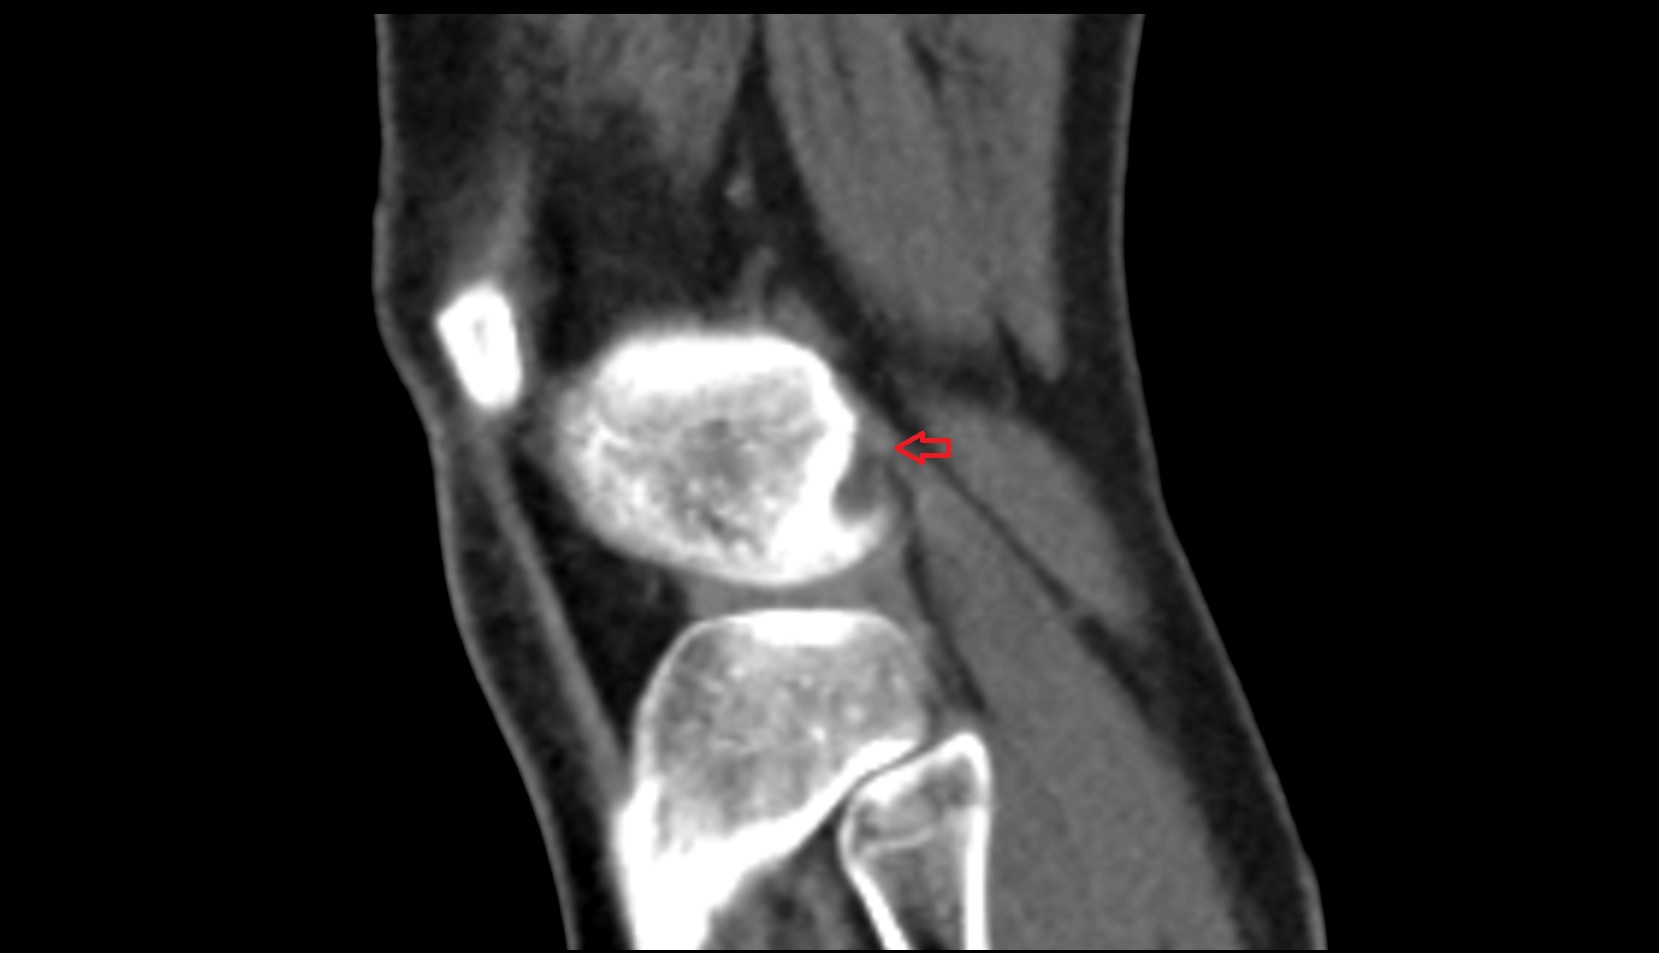

- Lateral condyle of femur

- Medial condyle of femur

- Femoral condyle articular cartilage

- Tibial condyle articular cartilage

- Tibia

- Fibula

- Head of fibula

- Knee Joint